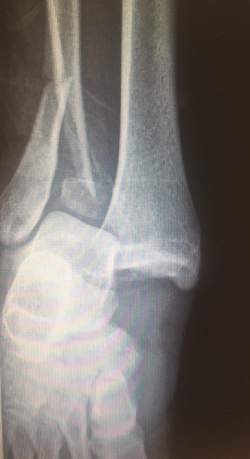

Figura 2. Luxación superior del astrágalo por lesión completa de la sindesmosis tibioperonea inferior (lesión de log splitter).